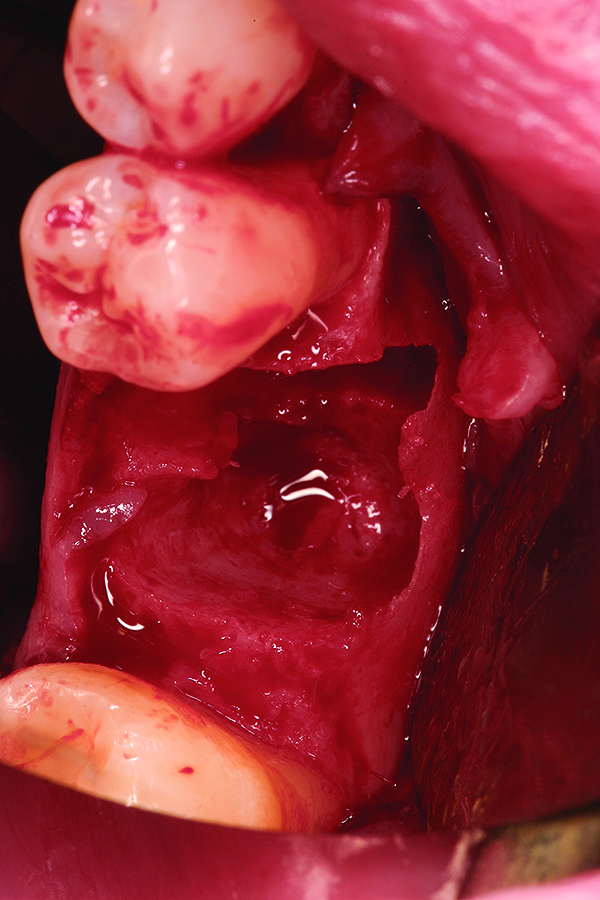

Fig 2. Atraumatic extraction of hopeless mandibular first and second molars.

Figure 2

Fig 9. Note the significant osseous defect in the buccal osseous wall following atraumatic tooth extraction.

Figure 9